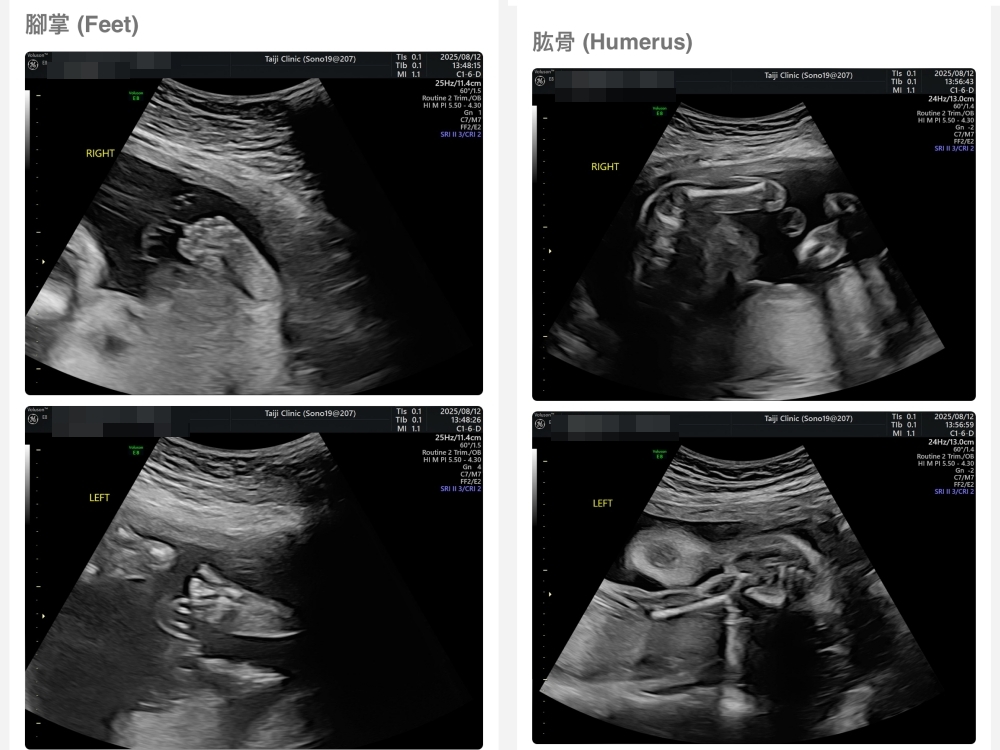

【台兒|高層次超音波|檢查結果】

▲離開診所後會收到MAIL,我們14:05離開,大約是16:45收到mail,裡面會有滿滿的超音波照片,紀錄的很詳細!也會提供紙本的報告,可以給日後產檢的醫師做參考👌